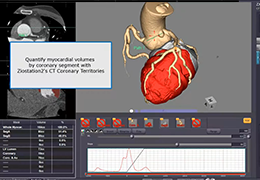

Performs 3D reconstruction and volume rendering.

Multi-planar slicing.

Oblique slicing.

Side-by-side comparative assessment for pre- and post-operative scans.